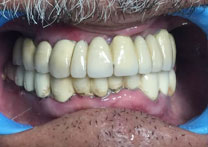

(9) Metal Ceramic Crowns

Before Treatment

After Treatment

Mr. Shiv Narayan Singh,aged 78yrs, came with a concern of multiple broken and mobile teeth with difficulty in chewing food. So, multiple RCTs followed by metal-ceramic crowns were delivered to the patient ,restoring his beautiful smile.